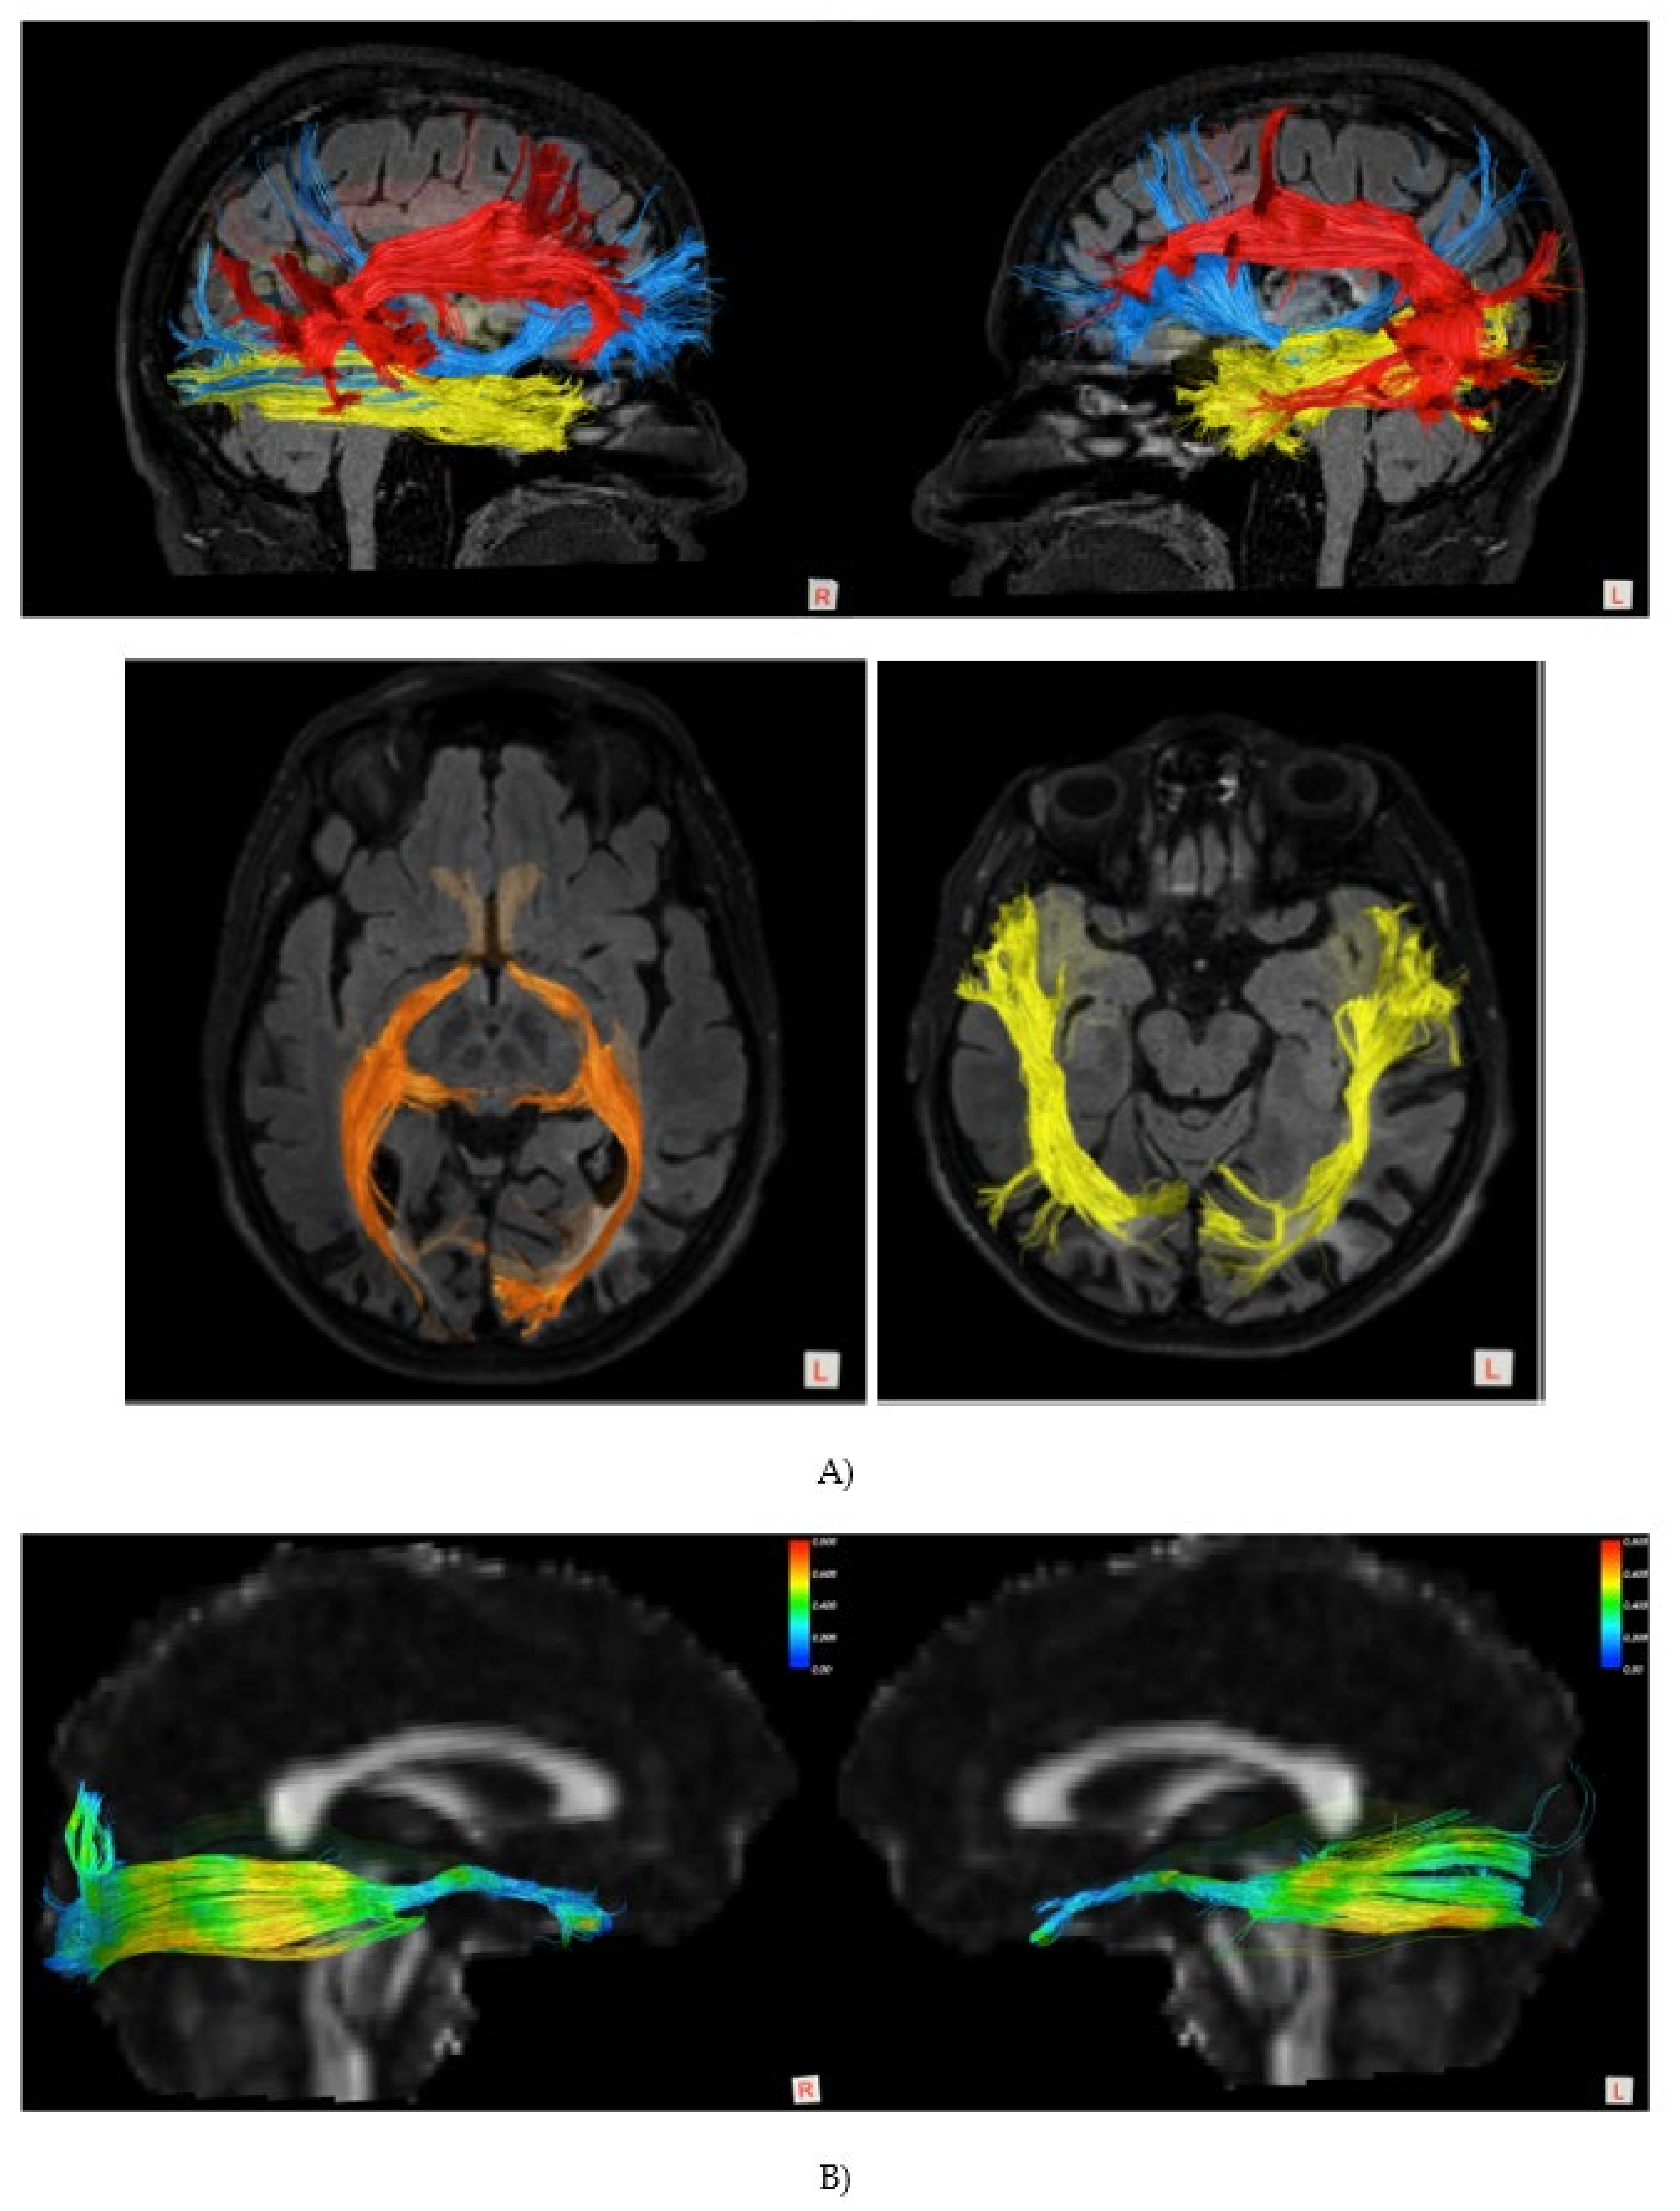

- Pieri, V.; Sanvito, F.; Riva, M.; Petrini, A.; Rancoita, P.M.V.; Cirillo, S.; Iadanza, A.; Bello, L.; Castellano, A.; Falini, A. Along-tract statistics of neurite orientation dispersion and density imaging diffusion metrics to enhance MR tractography quantitative analysis in healthy controls and in patients with brain tumors. Hum. Brain Mapp. 2020, 42, 1268–1286. [Google Scholar] [CrossRef]